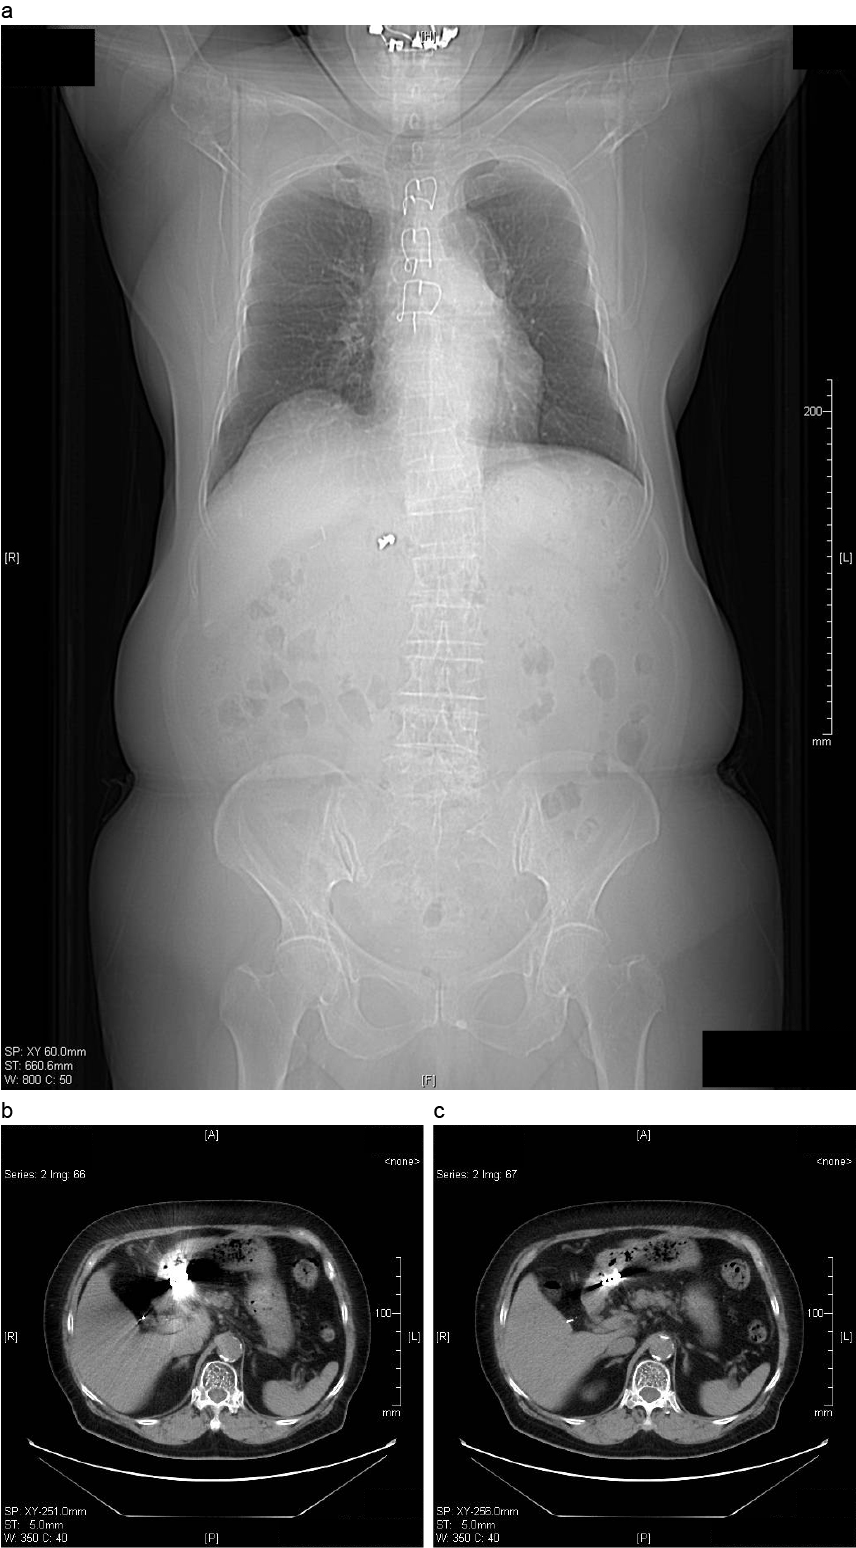

直腸異物(スプレー缶)例

a:直腸内に20cm×6cmのスプレー缶を認める、穿孔や腸閉塞の所見はなし。

b:同上

c:直腸周囲に炎症の波及が疑われた。

出典